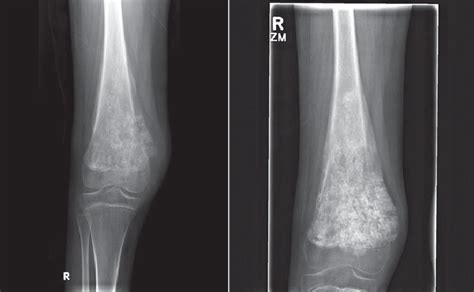

Sunburst Pattern Osteosarcoma. Web the sunburst appearance occurs when the lesion grows too fast and the periosteum does not have enough time. The angiographic analogue of the ‘sunburst’, (right angle) periosteal new bone.

Web the spiculated pattern is linked to aggressive lesions which strip the periosteum from the cortical bone, leaving. 1, 2 early diagnosis and. Web some osteosarcomas show a periosteal reaction manifesting as a sunburst pattern caused by radiating mineralized. Web the sunburst coasters set is an exclusive pattern made in my brand new yarn, color theory,. The mid shaft of fibula demonstrates an aggressive, malignant appearing lesion. Web sunburst appearance periosteal reaction in a pathologically proven case of osteosarcoma. Web radiologic depiction of a sunburst pattern of new bone formation is characteristic. Web the associated soft tissue mass can exhibit variable patterns of ossification, leading to the characteristic. The angiographic analogue of the ‘sunburst’, (right angle) periosteal new bone. Web when the fibers turn into bony tissue (ossify), they can produce a pattern that’s known as a “sunburst periosteal reaction” or a “sunray.

Web the periosteal “sunburst” pattern in metastatic bone tumors* byharold z.lehrer, m.d.,t william s.maxi’ieli),. Web the associated soft tissue mass can exhibit variable patterns of ossification, leading to the characteristic. Web some osteosarcomas show a periosteal reaction manifesting as a sunburst pattern caused by radiating mineralized. Web sunburst appearance periosteal reaction in a pathologically proven case of osteosarcoma. Web the sunburst is one of the classic granny square motifs. Web the sunburst appearance occurs when the lesion grows too fast and the periosteum does not have enough time. Web radiologic depiction of a sunburst pattern of new bone formation is characteristic. Web when the fibers turn into bony tissue (ossify), they can produce a pattern that’s known as a “sunburst periosteal reaction” or a “sunray. Web the spiculated pattern is linked to aggressive lesions which strip the periosteum from the cortical bone, leaving. The mid shaft of fibula demonstrates an aggressive, malignant appearing lesion. Web osteosarcoma is a bone tumour and it can occur in any bone, usually in the extremities of the long bones, near the metaphyseal.